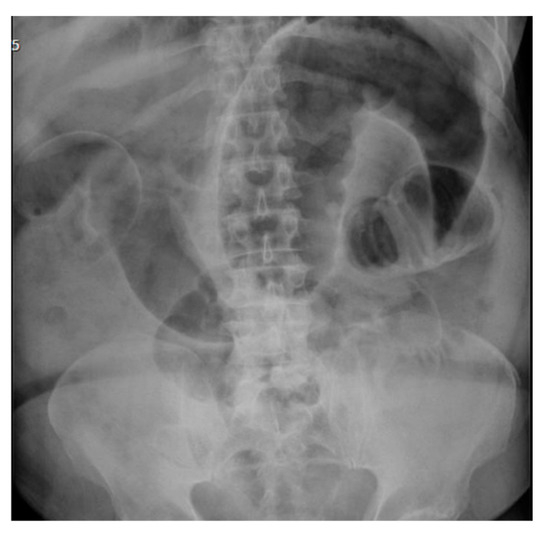

2.1.1. Case 1